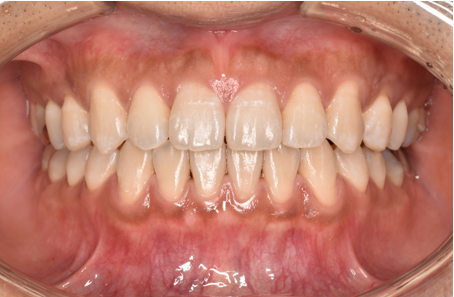

治療後

| 術後の経過・現在の様子 | 予定通りに治療が完了しました。 患者様にも「思っていたより痛みもなく、綺麗に並んで嬉しい」とご満足いただけました。 |